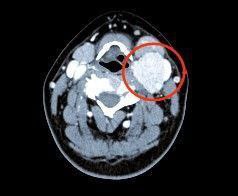

Нижегородские врачи прооперировали женщину с редкой опухолью шеи

Каротидная хемодектома в области шеи – одна из самых редких сосудистых опухолей. Обычно они возникают в молодости и долгое время себя не проявляют.

Медики Нижегородского онкоцентра и кардиохирургической больницы им.Б.А. Королёва ювелирно удалили опухоль, несмотря на то, что операция осложнялась вмешательством в сосуды, питающие головной мозг. На контрольном обследовании рецидива опухоли не обнаружено, сообщает главный редактор ИА "Стационар-пресс" Алексей Никонов.